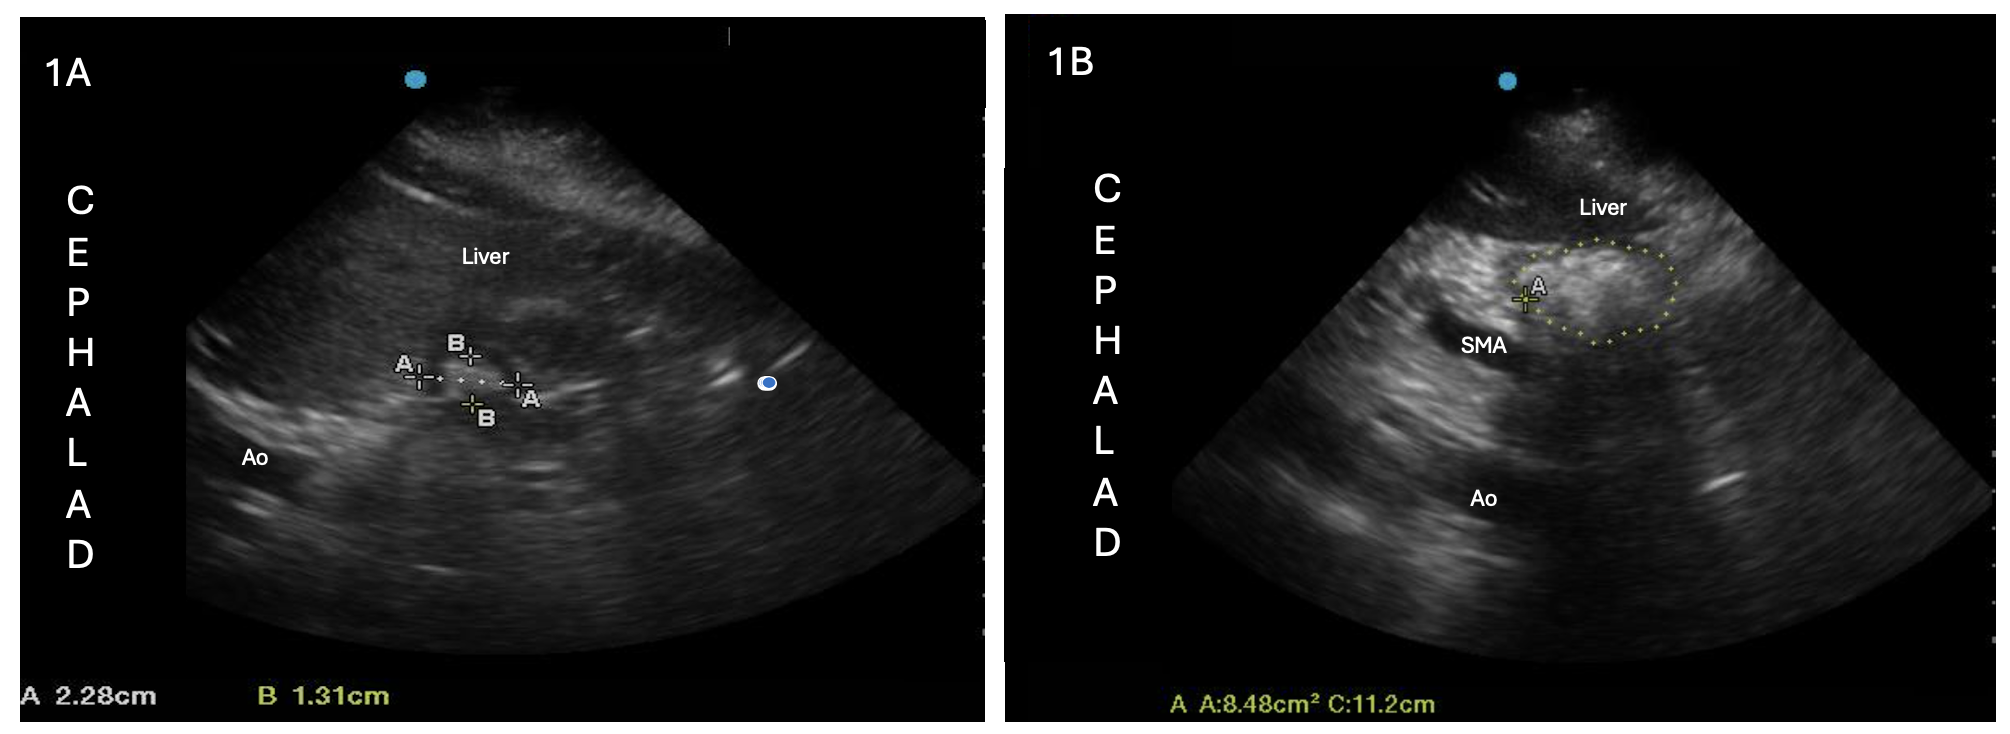

Results: Of the 12 patients, 8 (66.7%) had non-empty stomachs on gastric ultrasound after an overnight fast (Figure 1). Of those 8 patients, 7 were interpreted as solid-filled stomachs, and 1 was rated as having liquid contents (liquid volume/patient weight of 2.10 mL/kg, which is deemed as “unsafe” by the Perlas Equation (1)). The 4 patients with empty stomachs had an average time since last meal of 17.56 hours (95% CI 9.64 – 25.48), compared to 11.88 hours (10.24 – 13.52) in the 8 non-empty stomachs. Those with non-empty stomachs were more often older, less fasting time, with higher doses and longer duration of methadone, and higher percent Hispanic (Table 1). Empty subjects had comparatively smaller mean supine and RLD antral CSAs of 3.93 cm2 (2.16 – 5.70) and 6.22 cm2 (4.96 – 7.48), respectively, while non-empty subjects had mean supine and RLD antral CSAs of 8.59 cm2 (5.467 – 11.72) and 10.4 cm2 (5.59 – 15.21), respectively.